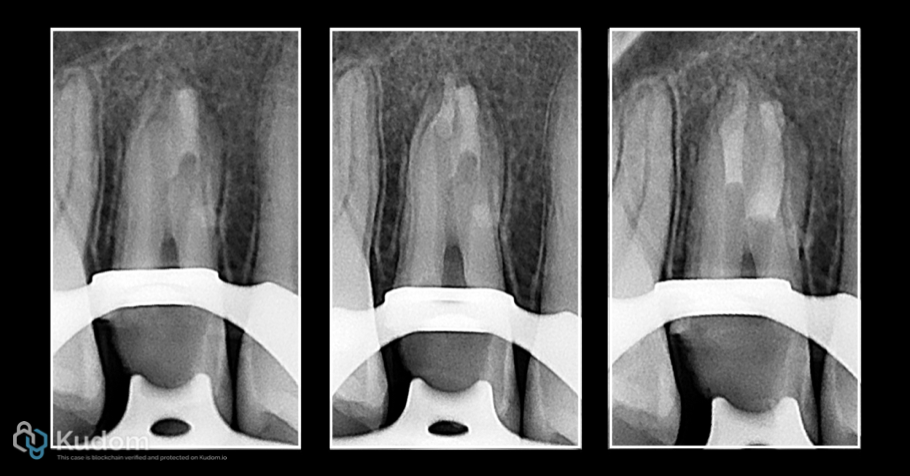

Fig. 2

Upper 2nd Premolar had RCT before 3 week ago.

Over obturation with poor apical control in both buccal and palatal canals